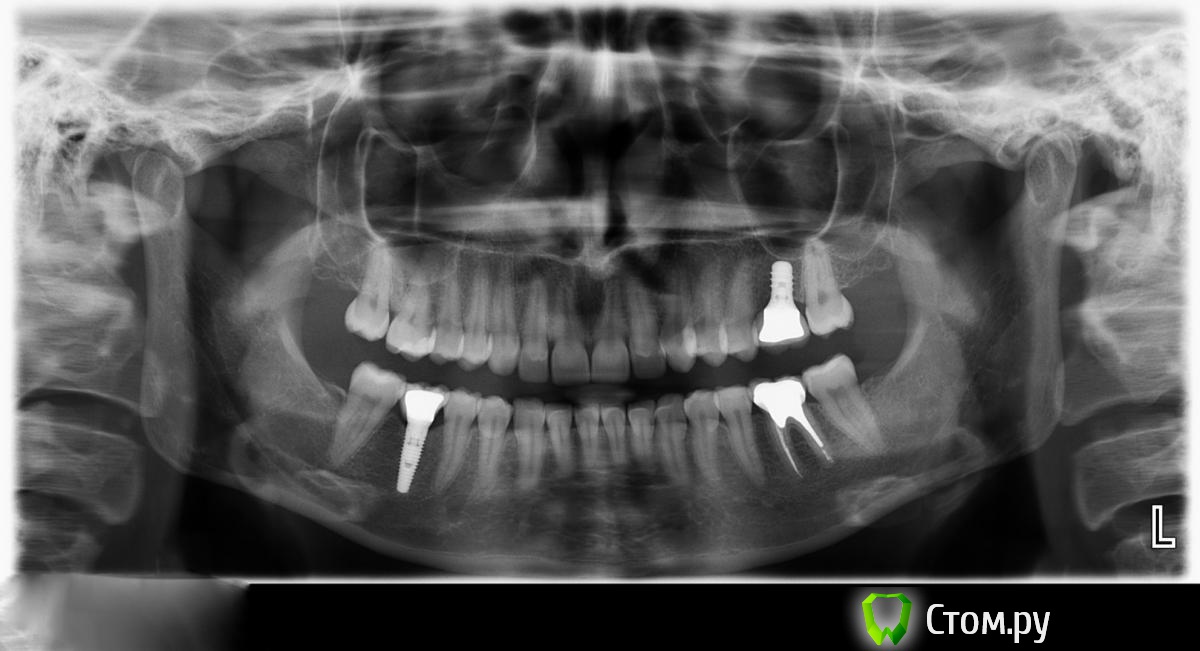

IvanK Опубликовано 17 января, 2014 Поделиться Опубликовано 17 января, 2014 В Вашем случае, я бы посоветовал сходить еще к паре Врачей для очного осмотра.+ панорамный снимок Ссылка на комментарий

Korn05 Опубликовано 20 января, 2014 Автор Поделиться Опубликовано 20 января, 2014 Панорамный снимок. Посмотрите, пожалуйста. Врач считает, что все ок. Ссылка на комментарий

IvanK Опубликовано 20 января, 2014 Поделиться Опубликовано 20 января, 2014 тоже криминала не вижу.. 1 Ссылка на комментарий

Bier Опубликовано 21 января, 2014 Поделиться Опубликовано 21 января, 2014 Кт еще можно сделать Ссылка на комментарий